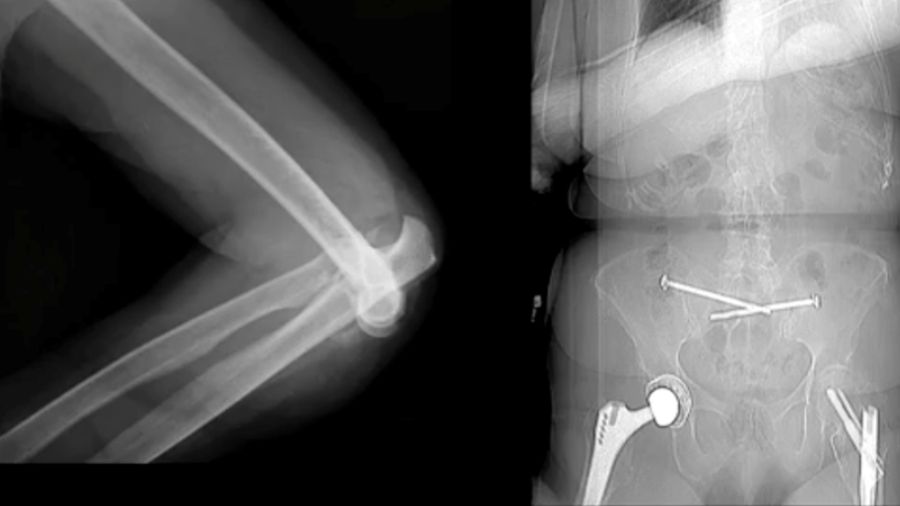

Case 4: 94-year-old woman

In this case, a total elbow prosthesis was chosen for a 94-year-old patient with severe trauma. The prosthesis was repositioned but eventually dislocated again, highlighting the complexities of managing such advanced injuries in older patients.

Case 5: 46-year-old male, athlete

A 46-year-old athlete with a comminuted coronoid fracture and severely damaged radial head required multiple surgeries after an overstuffed radial head prosthesis caused complications. The final solution was a total elbow prosthesis, underscoring the importance of careful prosthesis sizing and ligament repair.

In conclusion, while conservative treatment might be an option for some terrible triad cases, careful attention to radial column stability, ligament repair, and coronoid fixation is critical to achieving a durable result. Early mobilization and a well-executed repair plan are key to a successful recovery. Special attention should be paid to:

- Concentric joint reduction is crucial for a stable elbow joint.

- Radial column stability is essential; avoid any issues with pronation-supination.

- Evaluate the coronoid—is it just the tip or a more extensive fracture?

- Aim for a stable range of motion (30-40° flexion is acceptable) to avoid subluxation.